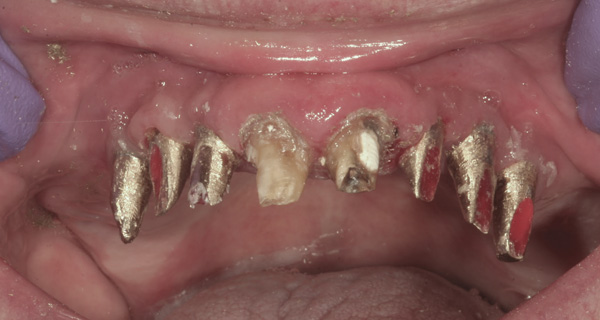

Results: A decision was made to re-prepare all of the abutments intraorally (Figure 3) so that all abutment margins would be at or below the gingival margin. (Of note, teeth Nos. 8 and 9, also shown in Figure 3, were later submerged for the case to be fully implant-supported.) While re-preparation greatly improved the esthetics of the final result, it required retraction cord placement, new impressions, and new castings.

(Note: A separate but similar type of case shown in Figure 4 and Figure 5 further illustrates intraoral abutment re-preparation.)

Figure 3 Abutments re-prepared intraorally.

Figure 3

Figure 4 Following osseointegration of an implant at No. 12, recession was observed at the fixture-level impression stage of No. 13; it was decided to re-prepare the margins of the CAD/CAM custom abutment of implant No. 12. Retraction cord was placed prior to preparation to avoid tissue injury and improve visibility of both tooth No. 11 and the implant custom abutment margin. As expected, recession was greater along the distal side of abutment No. 12, adjacent to the healed extraction/newer implant site.

Figure 4